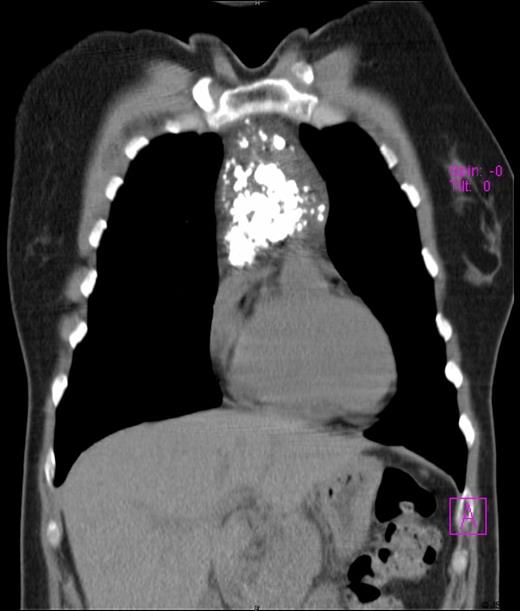

A 45-year-old female presented with symptoms of gastroesophageal reflux. Her past medical history included hypothyroidism and endometriosis. The patient reported fatigue over several months, but denied any chest pain, fever, dyspnea, cough or weight loss. Physical examination was unremarkable. She underwent a double-contrast upper GI series which revealed no abnormalities in the oesophagus or stomach but was suggestive of an intra-thoracic mass. Chest radiograph noted a heavily calcified mass in the anterior mediastinum. Computed tomography (CT) scan of the thorax revealed a well defined mass of mixed density with speckled calcifications located in the antero-superior mediastinum. The lesion extended from the sternal notch to the level of the aortic root (Figures 1a and 1b). Laboratory tests including β-HCG, α-fetoprotein, CEA, LDH and TSH were all within normal limits and pulmonary function tests were normal. Preoperatively, the working diagnosis was a thymoma, although not typical in appearance, and thus surgical resection was planned. The operation was performed through a median sternotomy. A radical “en-bloc” resection of the tumour, mediastinal fat, thymus, pericardium and pleura was carried out. There was no evidence of tumour dissemination in the pericardium or pleural cavities or metastatic lymphadenopathy. Macroscopically, the tumour was completely resected with negative margins. The patient had an uneventful postoperative course and was discharged one week after surgery. A 24 month follow-up has shown no recurrence of the disease.

Preoperative chest computed tomography scan revealing a large mediastinal mass - Axial view

Preoperative chest computed tomography scan revealing a large mediastinal mass - Coronal view